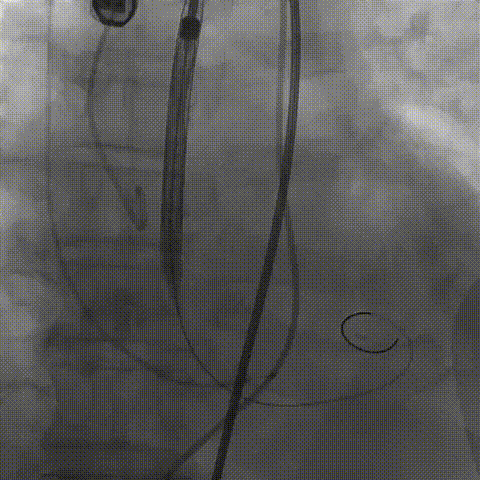

术中影像

根部造影;直头导丝顺利跨瓣

23mm球囊预扩,冠脉显影正常;输送器顺利过弓

初次释放,无冠窦畸形猪尾难以到达窦底,定位带来挑战;释放至工作位,瓣膜(AV29)位置偏低

瓣膜(AV29)完全回收后重新定位释放

瓣膜(AV29)工作位正交体位造影位置良好,左冠显影正常

瓣膜(AV29)完全脱钩释放后23mm球囊充分后扩,冠脉灌注良好

最后造影